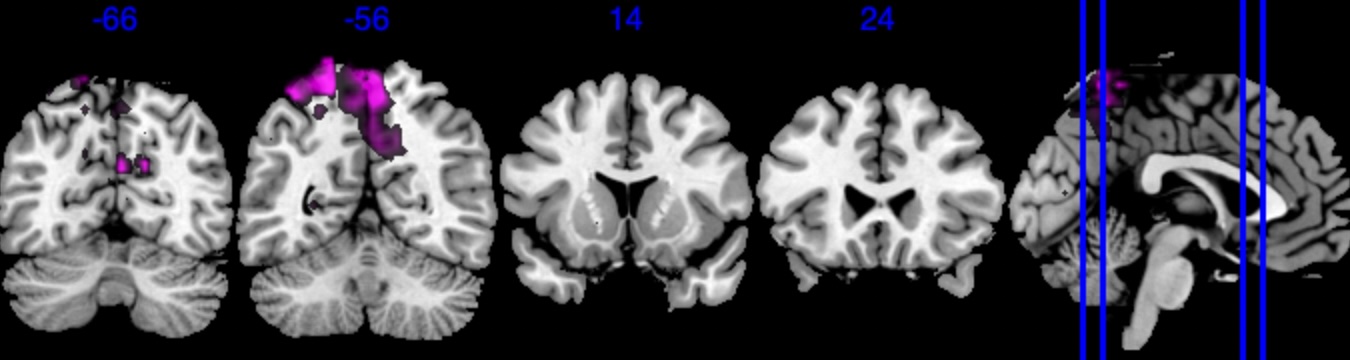

We performed 100,000 iterations for the outcome model (1), discarding the first 50% as burn-in and thinning to retain 1,000 posterior samples. For the mediator model (2), we ran 40,000 iterations with a 30,000 burn-in, thinning every 10 iterations to obtain 1,000 posterior samples. Table 3 gives a summary of both the overall NIE and NDE and the top seven regions identified with the largest number of active voxels. The definition of NIE in each region is , where is the collection of all voxels in region . The rule for selecting the active voxels is based on cutting the posterior inclusion probability (PIP) at 50%, and the three regions with active voxels are reported in Table 3. Due to the very small effect sizes and low signal-to-noise ratio, we also include regions with voxels’ PIP greater than 10%. The posterior of NDE has a mean of 0.27 with the 95% credible interval . The posterior of NIE has a mean of 0.0885 with the 95% credible interval . The total effect of parental education level on general cognitive ability score is 0.36, with 95% credible interval (0.29,0.45). This suggests that parents with college degrees have a positive impact on children’s cognitive abilities, and about 25% of the effect is mediated through brain cognitive development. Figure 5 shows the estimated activation regions and the NIE in coronal view slides. Among the top identified activation regions, the most interesting is the left precuneus, which plays a key role in episodic memory, visuospatial processing, and self-consciousness (lou2004parietal; wallentin2006parallel). This region has been consistently implicated in cognitive processes related to memory retrieval and spatial awareness, which are crucial components of children’s cognitive development. In addition, other identified regions, such as the left inferior parietal region and the left postcentral gyrus, are associated with the interpretation of sensory information (radua2010neural; diguiseppi2023neuroanatomy). These regions are involved in integrating and processing sensory inputs, which are essential for tasks that require coordination between perception and cognition, such as working memory and executive function. These findings align with existing literature on the neural correlates of cognitive function, particularly in children. By identifying regions that have been consistently associated with cognitive processes, our results not only demonstrate the scientific validity of the BIMA approach but also provide meaningful insights into the brain areas that underlie cognitive abilities as captured by the ABCD study.

| Posterior inclusion probability (color range ) |

![]() |

| Positive posterior mean of the spatial mediation effects (color range ) |

| Negative posterior mean of the spatial mediation effects (color range ) |